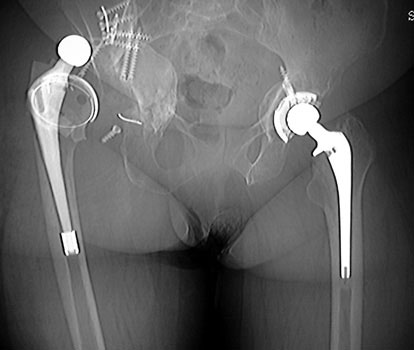

Dislocated bipolar hemiarthroplasties in 2 different patients.